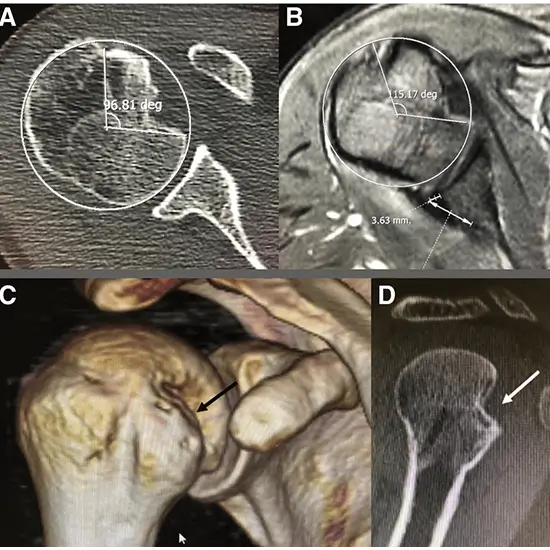

A shoulder computed tomography scan (CT) uses specialised X-ray cameras to create cross-sectional images of the shoulder. This scan allows doctors to see the bones and soft tissues in the shoulder and detect any abnormalities. The CT scan may also aid in the detection of tumours and blood clots.

• identify muscle, tendon, or ligament tears

• Identify joint inflammation; diagnose injuries caused by trauma, such as a dislocation or fracture